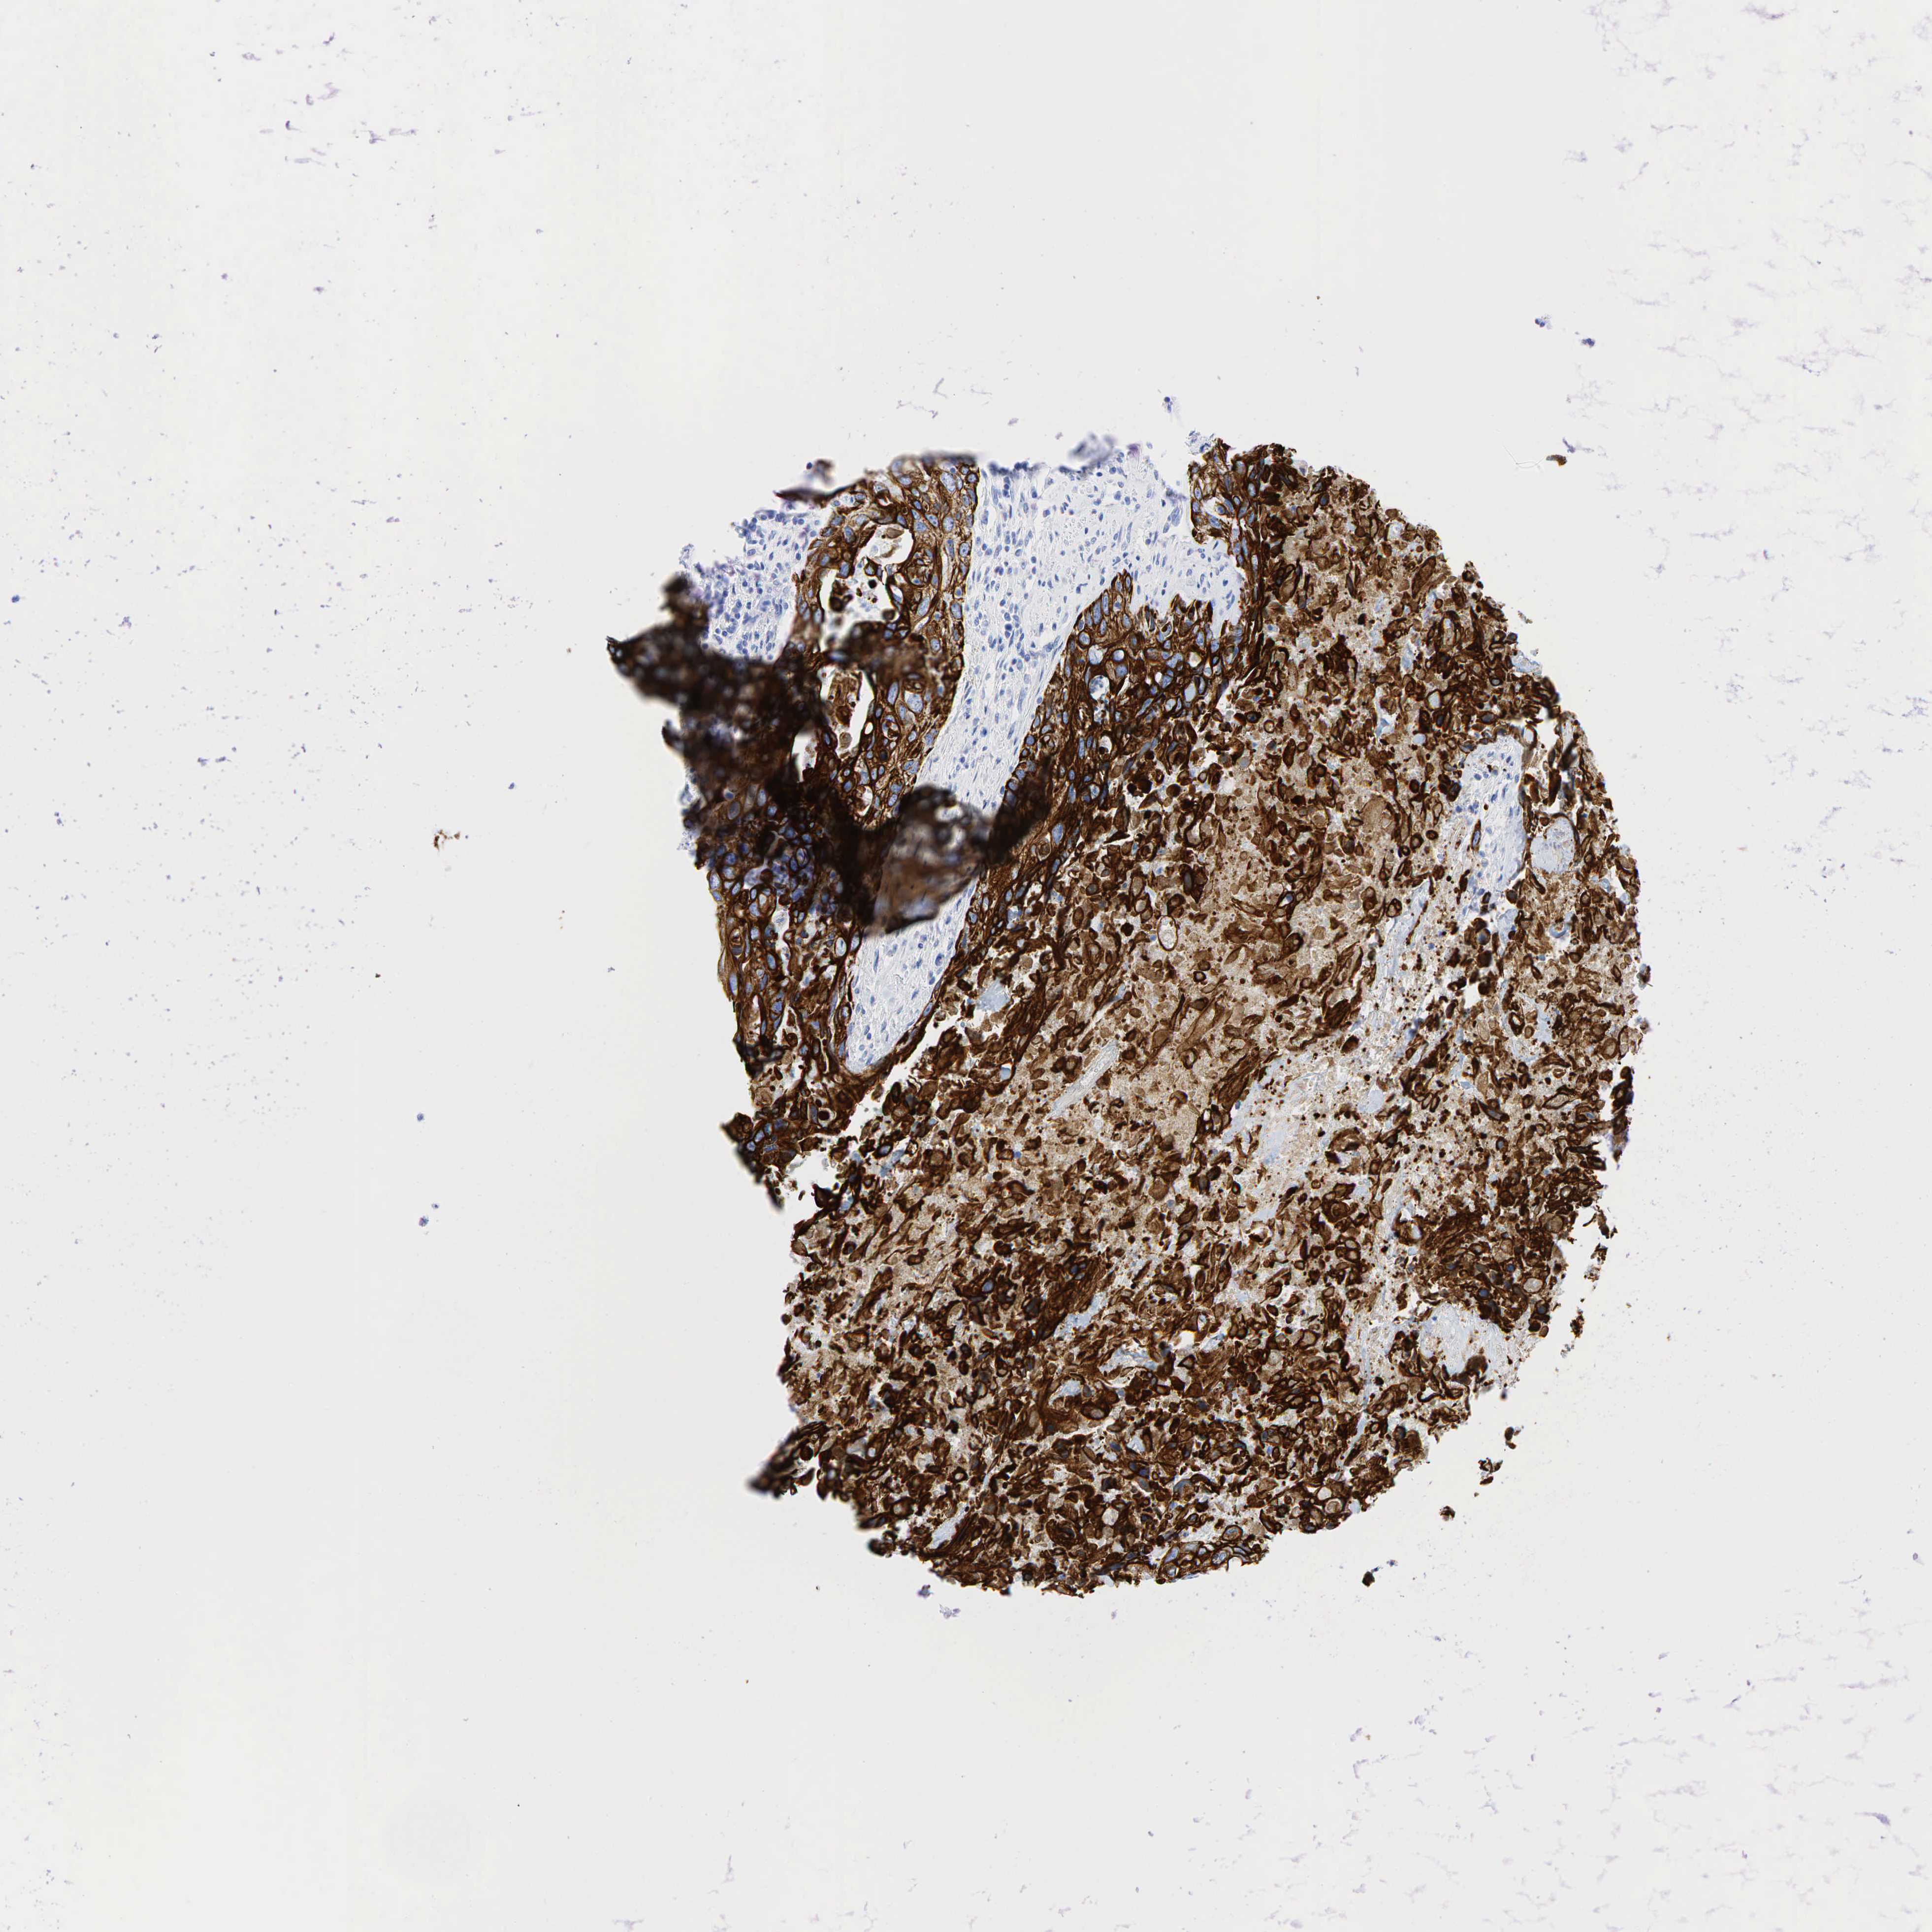

UROTHELIAL CANCER - Protein expressioni

A mouse-over function shows sample information and annotation data. Click on an image to view it in a full screen mode. Samples can be filtered based on level of antibody staining by selecting one or several of the following categories: high, medium, low and not detected. The assay and annotation is described here.

Antibody stainingi

Antibody staining in the annotated cell types in the current human tissue is reported as not detected, low, medium, or high, based on conventional immunohistochemistry profiling in selected tissues. This score is based on the combination of the staining intensity and fraction of stained cells.

Each image is clickable and will lead to virtual microscopy that enables deeper exploration of all samples and also displays staining intensity scores, fraction scores and subcellular localization as well as patient and tissue information for each sample.

Antibody HPA002465

Antibody CAB000031

Staining

High

Medium

Low

Not detected

Intensity

Strong

Moderate

Weak

Negative

Quantity

>75%

75%-25%

<25%

None

Location

Nuclear

Cytoplasmic/membranous

Cytoplasmic/membranous,nuclear

Urothelial carcinoma, High grade

Urothelial carcinoma, Low grade

Adenocarcinoma, NOS